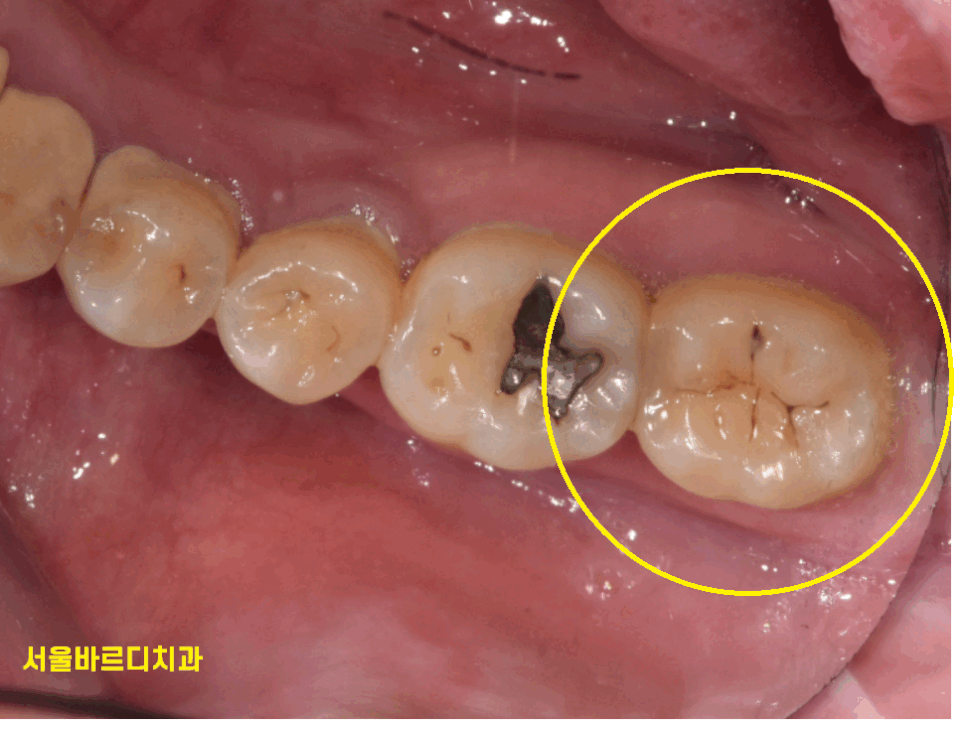

이를 닦다가 거울을 보았는데

검은색 무언가를 보았다면..?

이거... 검은 점 충치 아니야???

거울을 보다보면

이런 검은 점을 보신 적 있을겁니다!

240401

그럼 이건 충치일까요?

방금 보았던 충치보다 검정색이

좀더 진하게 보이죠~?

충치는 맞습니다!

그렇지만 역시나

치료를 안해도 된다!!!

단! 관리만 잘해준다면!! (핵심)

관리해준다면 충치가 정지합니다.

정지성 우식이라 표현하는데요

검은 점이 보인다고

모두 충치 치료를 할 필요는 없답니다.

길동 치과에서는 이런 검은 점 충치는

치료하지 않습니다.

정기검진을 통하여 지켜보고

충치가 커지거나 하였을 때 치료를 시작하죠~!